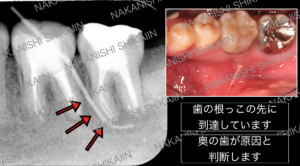

① どこの歯が膿んでいるかの判断

ニキビのようなものは、膿の出口です。

言い換えると、そこから膿が作り出される部位までつながっています。

そこに内視鏡のようなものを優しく挿入し、原因の場所を特定します。